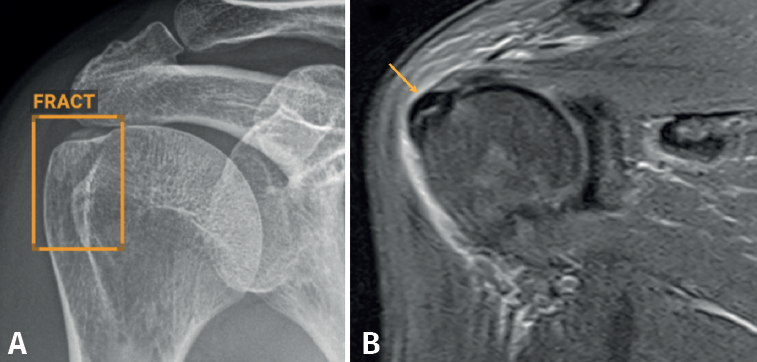

Aunque no hemos realizado un estudio de sensibilidad y especificidad por la complejidad que entraña en la práctica asistencial, consideramos que los resultados son satisfactorios, en línea con lo publicado en la literatura científica. Destacamos la eficacia del algoritmo en la detección de pequeñas fracturas arrancamiento (Figura 3), fracturas de radio distal y proximal (Figura 4), y fracturas múltiples (Figura 5).